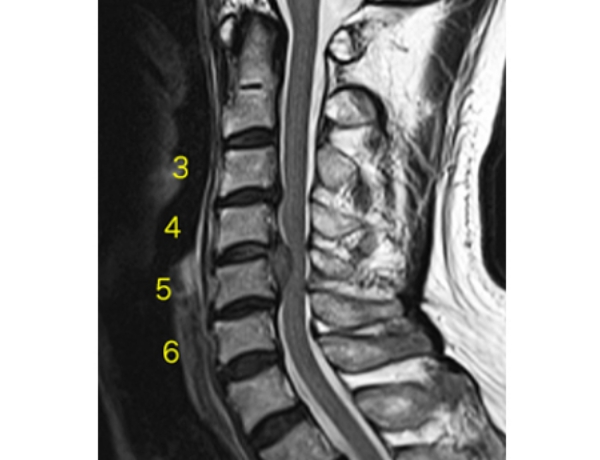

椎間板ヘルニア(頚椎)

61歳男性

第4、5頚椎間に髄核が大きく突出して脊髄を強く圧迫している